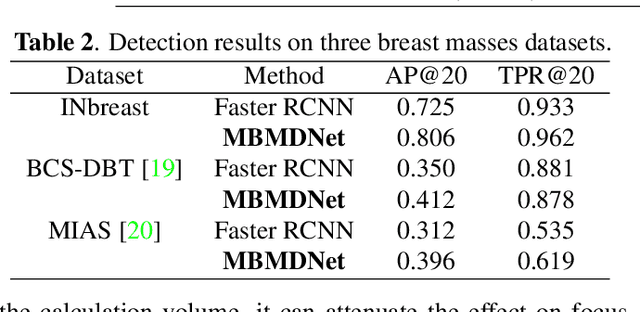

Multi-Head Feature Pyramid Networks for Breast Mass Detection

Feb 22, 2023

Analysis of X-ray images is one of the main tools to diagnose breast cancer. The ability to quickly and accurately detect the location of masses from the huge amount of image data is the key to reducing the morbidity and mortality of breast cancer. Currently, the main factor limiting the accuracy of breast mass detection is the unequal focus on the mass boxes, leading the network to focus too much on larger masses at the expense of smaller ones. In the paper, we propose the multi-head feature pyramid module (MHFPN) to solve the problem of unbalanced focus of target boxes during feature map fusion and design a multi-head breast mass detection network (MBMDnet). Experimental studies show that, comparing to the SOTA detection baselines, our method improves by 6.58% (in AP@50) and 5.4% (in TPR@50) on the commonly used INbreast dataset, while about 6-8% improvements (in AP@20) are also observed on the public MIAS and BCS-DBT datasets.